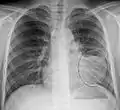

Left upper lobe pneumonia with a small pleural effusion.